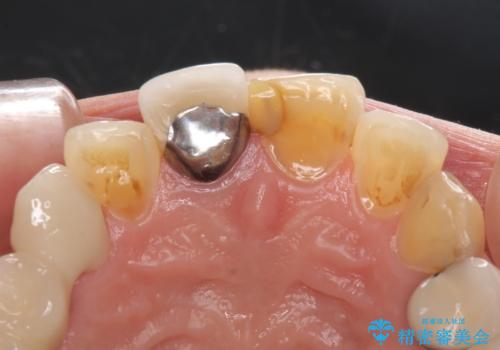

- 上の前歯2本が不調和であることを気にして来院された患者様です。

以前に前歯をぶつけた際、一方は神経を取り除いたためクラウンを装着し、もう一方は神経が残せたため一部修復をしていたとのことでした。

神経は残せていましたが、歯の色の変色が著しく、また広がった大きな形をしていたため、前歯2本をオールセラミッククラウンにて補綴することとしました。